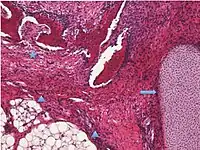

Surface epithelial-stromal tumorSerous tumor 25%18.5%Benign serous tumors of the right ovarian cyst are thinwalled unilocular cysts that are lined by ciliated pseudostratified cuboidal or columnar epithelium.[6]